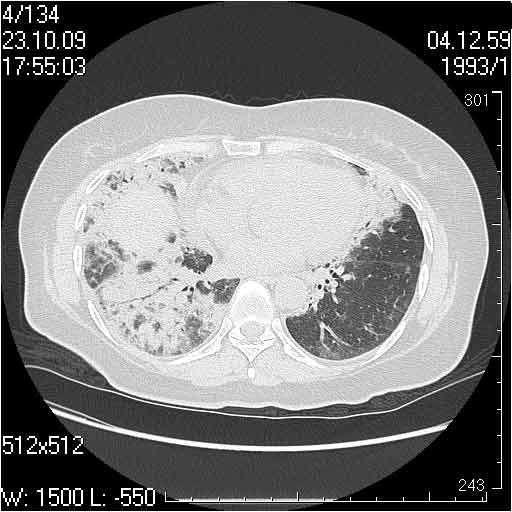

Случай №3

Женщина 51 год

Случай 3:смешанные изменения; подходят для интерстициальной пневмонии, тактика аналогична случаю 1.